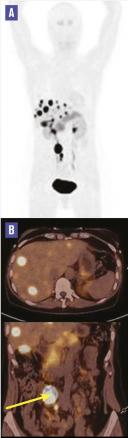

Cette femme de 52 ans était hospitalisée pour le bilan de flushs avec urticaire et épisodes de tachycardie avec hypotension artérielle, évoluant depuis 6 ans sans altération de l’état général. Les symptômes étaient pluriquotidiens, initialement rythmés par les repas et allaient en s’intensifiant, avec des épisodes de diarrhée motrice de résolution spontanée. Les antihistaminiques étaient sans effet. Hémogramme, ionogramme sanguin, transaminases, phosphatases alcalines, protéine C-réactive et catécholamines plasmatiques étaient normaux ; la sérotonine plasmatique était à 5 840 μmol/L (N < 1 134), l’acide 5-hydroxyindolacétique (5-HIAA) à 175 μmol/24h (N < 40) et la chromogranine A à 162 μg/L (N < 102). La tomodensitométrie thoraco-abdomino-pelvienne révélait de multiples hypodensités nodulaires du foie ; la TEP-TDM à la 18-fluoroDOPA montrait un hypermétabolisme intense de ces nodules et une masse ganglionnaire mésentérique droite avec adénopathies satellites, dont l’intensité était très en faveur d’une localisation secondaire de tumeur neuro-endocrine (TNE) ; elle montrait également un foyer hypermétabolique en projection de l’iléon évocateur d’une TNE primitive de l’iléon (v. figure). Le diagnostic de syndrome carcinoïde révélant une TNE avec métastases hépatiques était posé. Le traitement associait une chirurgie avec résection iléale et des injections d’analogue de la somatostatine. Les résultats anatomopathologiques confirmaient le diagnostic de TNE. L’évolution était favorable.

Le syndrome carcinoïde peut s’observer en cas de TNE qui, dans plus de 90 % des cas sont originaires de l’intestin moyen (du jéjunum distal au côlon droit) et métastatiques avec forte masse tumorale. Les TNE dérivées de l’intestin moyen sont des tumeurs rares, à croissance lente et de diagnostic souvent retardé car peu symptomatiques initialement en dehors d’une hypersécrétion hormonale. Le diagnostic de syndrome carcinoïde est évoqué sur des symptômes à type de flushs, diarrhée, bronchospasme, valvulopathie du cœur droit assicié à une augmentation de la concentration des 5-HIAA urinaires. Dans les TNE de l’intestin grêle, le syndrome carcinoïde est très fréquemment révélateur de métastases hépatiques. L’enquête associe des techniques d’imagerie classique (TDM, IRM hépatique) et fonctionnelle (TEP à la FDOPA), plus performante que la scintigraphie aux récepteurs de la somatostatine pour les TNE dérivées de l’intestin moyen.